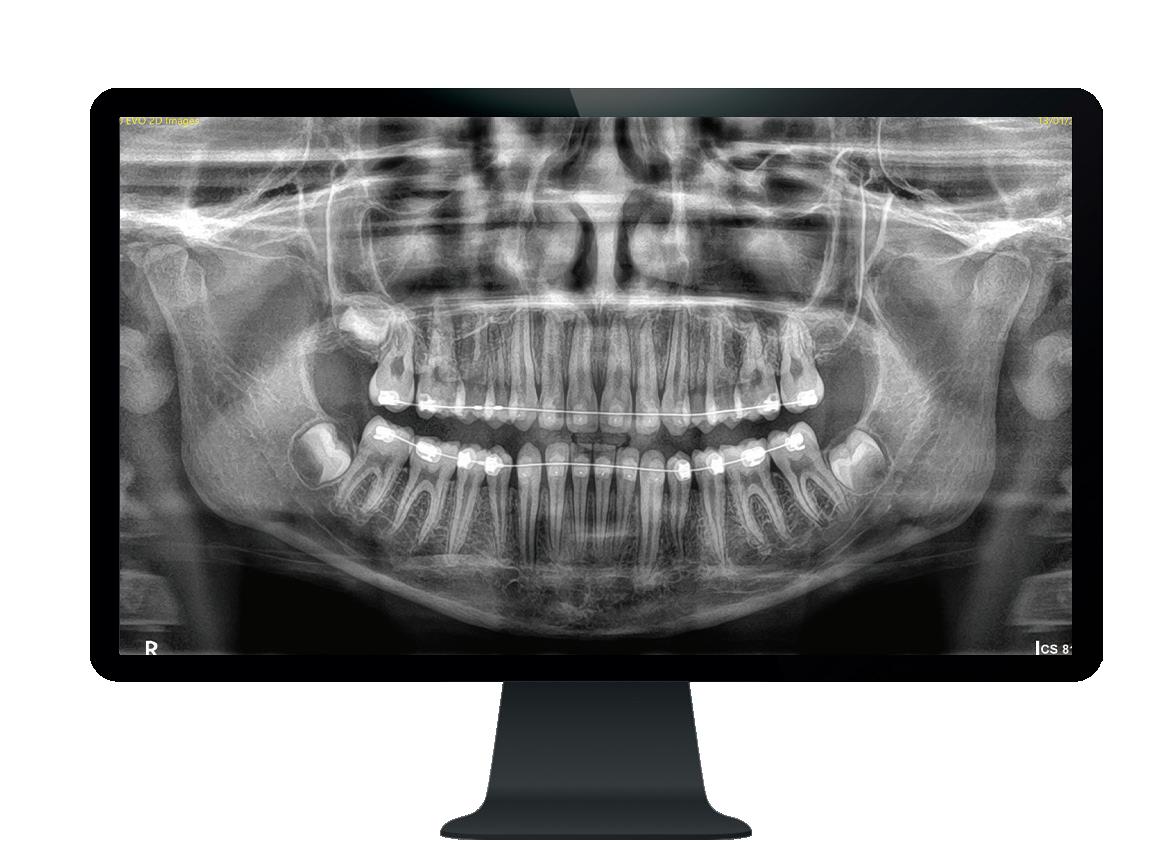

Ny, trådløs endomotor gir maksimal valgfrihet!

Nye Sendoline Endo Motor kan brukes med både roterende og resiprokerende filsystemer!

Stor valgfrihet! Bruk den bare som endomotor, som endomotor med apekslokator eller bare som lokator.

Vinkelstykket har slank, smal hals og et lite hode som kan roteres 360°. Dette gir deg enda bedre og enklere tilgjengelighet i munnen, med optimal sikt.